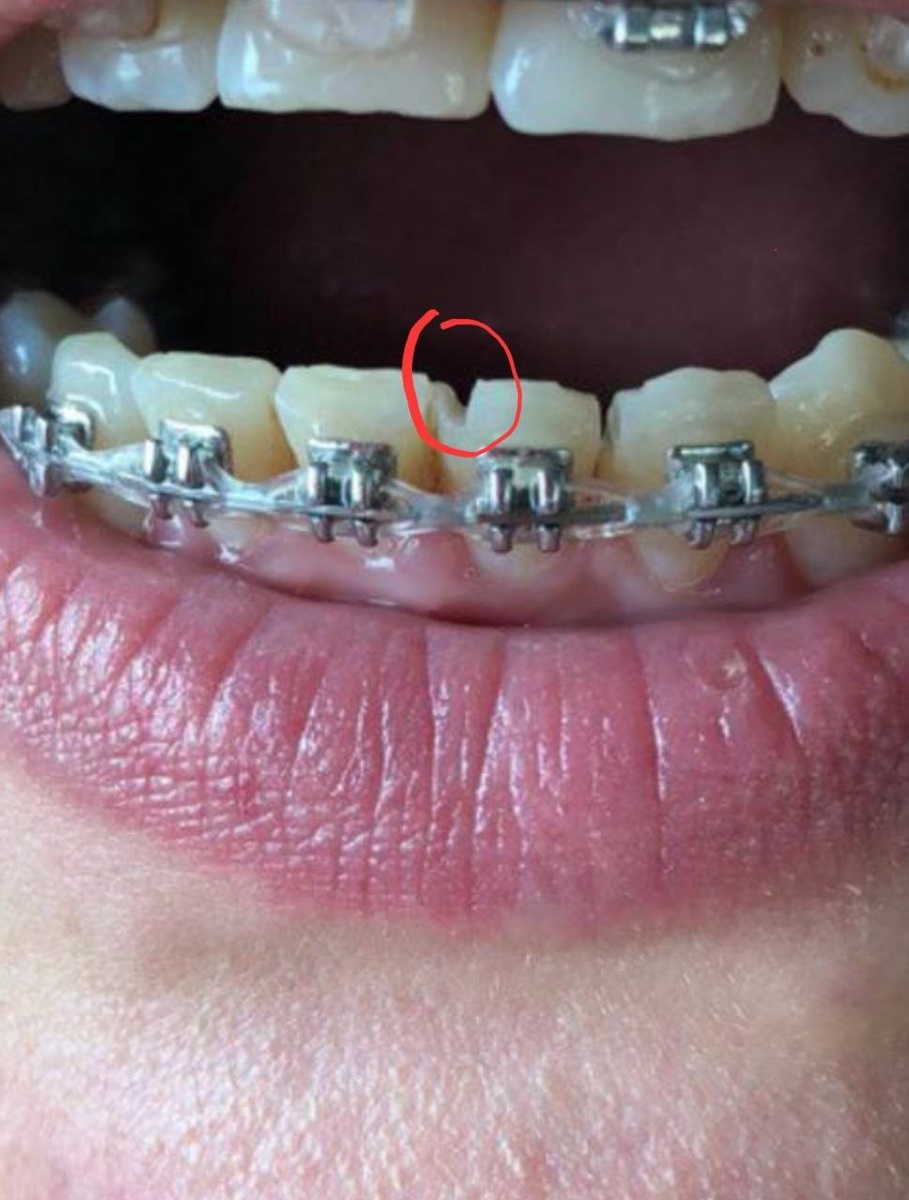

Мой прикус до исправления - жуть